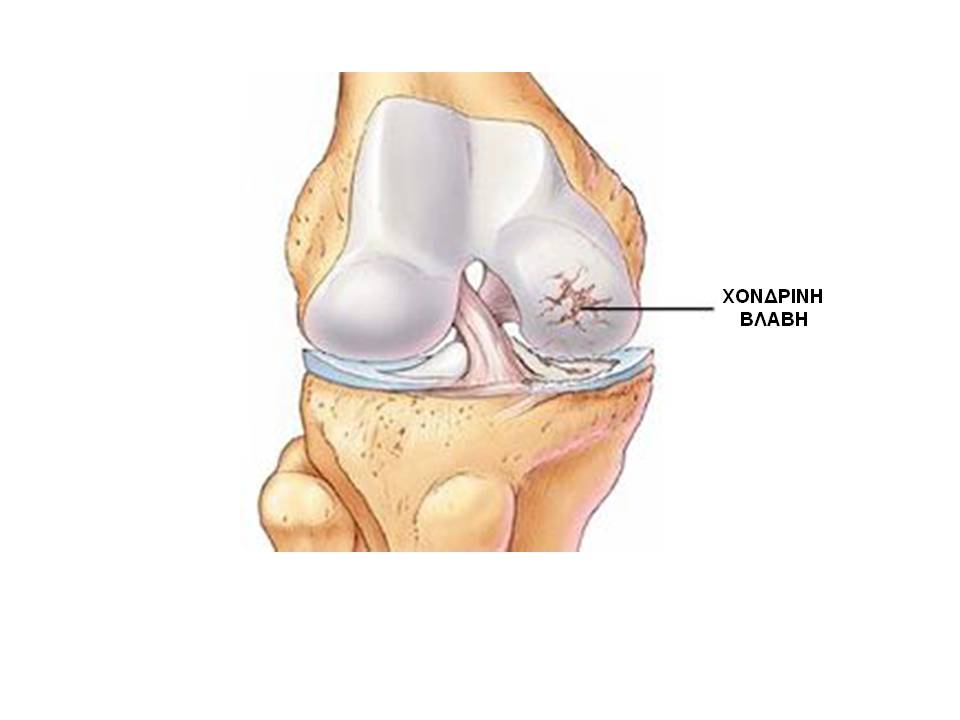

Χόνδρινες και οστεοχόνδρινες βλάβες γόνατος

Ο αρθρικός χόνδρος είναι ένας μαλακός, λείος και εξαιρετικά ανθεκτικός ιστός που καλύπτει τις αρθρικές επιφάνειες των οστών. Η παρουσία του εξασφαλίζει την ομαλή κύλιση των αρθρικών επιφανειών καθώς και την απορρόφηση φορτίων.

Η βλάβη του αρθρικού χόνδρου είναι συνήθως αποτέλεσμα επαναλαμβανόμενων μικροτραυματισμών (εκφύλιση) ή ενός σημαντικού τραυματικού επεισοδίου, όπως άμβλυνση, συχνά σε έντονη αθλητική δραστηριότητα.